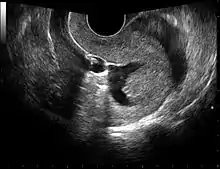

Sonohysterography

Sonohysterography. The sterile saline instilled into the cavity of the uterus is anechoic (rendered as dark in the middle of the image). It shows a normal endometrium as a hyperechoid (brighter) band around the cavity, in this case without any focal changes.

Sonohysterography is a specialized procedure by which fluid, usually sterile saline (then called saline infusion sonography or SIS), is instilled into the uterine cavity, and gynecologic sonography performed at the same time. A review in 2015 came to the conclusion that SIS is highly sensitive in the detection of intrauterine abnormalities in subfertile women, comparable to hysteroscopy. SIS is highly sensitive and specific test in the diagnosis of uterine polyps, submucous uterine fibroids, uterine anomalies and intrauterine adhesions (as part of Asherman's syndrome), and can be used as a screening tool for subfertile women prior to IVF treatment.[4]

Sonohysterography using a balloon catheter (seen in the middle of the image)